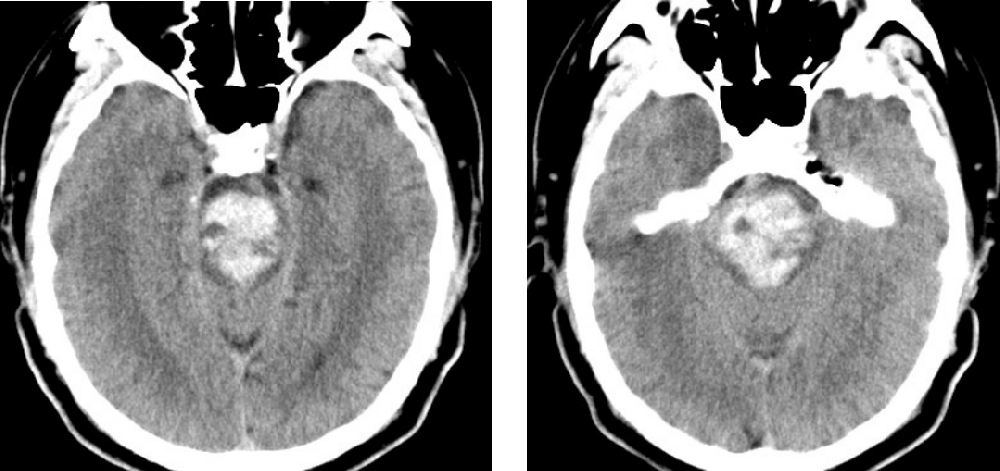

患者,男,45歲,1月2日因“突發昏迷1小時”被同事送至我院,急診CT檢查示腦干大量出血,出血量約15ml。此時患者已深度昏迷,各項生理反射消失,自主呼吸不穩定,肢體強直并出現中樞性高熱,體溫40℃。因病情危重、隨時可能出現呼吸心跳驟停,緊急收入重癥監護室,給予氣管插管、呼吸機通氣,維持各項生命指標治療。

附手術前患者顱腦CT: